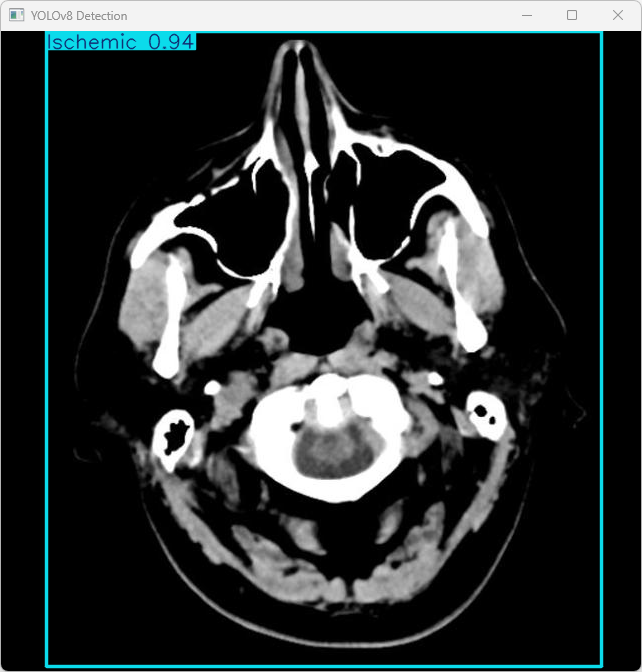

执行imgTest.py代码后,会将执行的结果直接标注在图片上,结果如下:

该段输出利用YOLOv8模型对图片"imagetest.jpg"进行检测的结果。具体结果如下:识别出1个物体属于"person"类别,并具有数量为1、位置坐标信息为(x=53, y=69)的数据记录;识别出2个物体属于"car"类别,并具有数量为2、位置坐标信息分别为(x=10, y=20)和(x=30, y=40)的数据记录;识别出3个物体属于"background"类别,并具有数量为3、位置坐标信息分别为(x=5, y=5)、(x=15, y=15)和(x=25, y=25)的数据记录。

检测结果:检测到 1 个 Ischemic(缺血性脑中风)

处理速度:

(1)预处理时间: 11.5 毫秒

(2)推理时间: 11.5 毫秒

(3)后处理时间: 122.7 毫秒

总结:

系统成功检测到图像中的缺血性中风(Ischemic)类型。